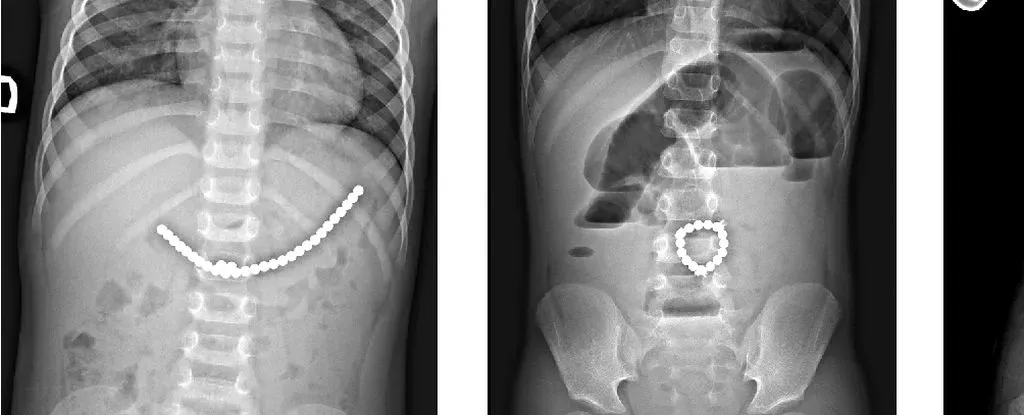

儿童吞食小型磁珠后的 X 光片。来源:Da?kevi?iūt? et al.,2017

手术中发现,这些磁铁链分别位于小肠不同区段及盲肠内。它们相互挤压,导致多处组织因血液供应不足而坏死,这种现象被称为压迫性坏死。